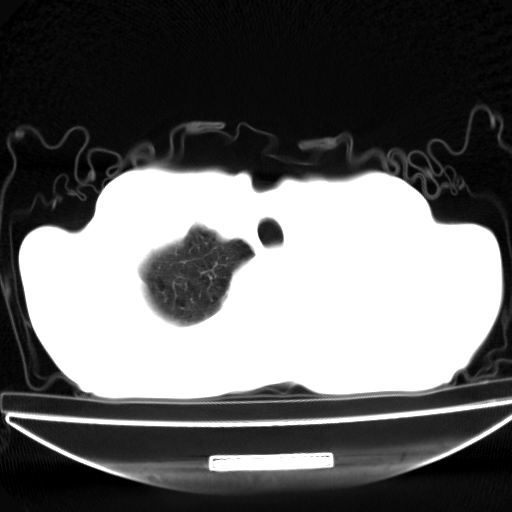

以下是引用杀毒软件在2009-4-28 17:58:00的发言:[br]考虑----左肺慢性肺脓肿形成继发上叶含气不良---抗炎后复查---待排肿瘤所致[br][br][本贴已被 杀毒软件 于 2009-4-28 18:01:26 修改过]